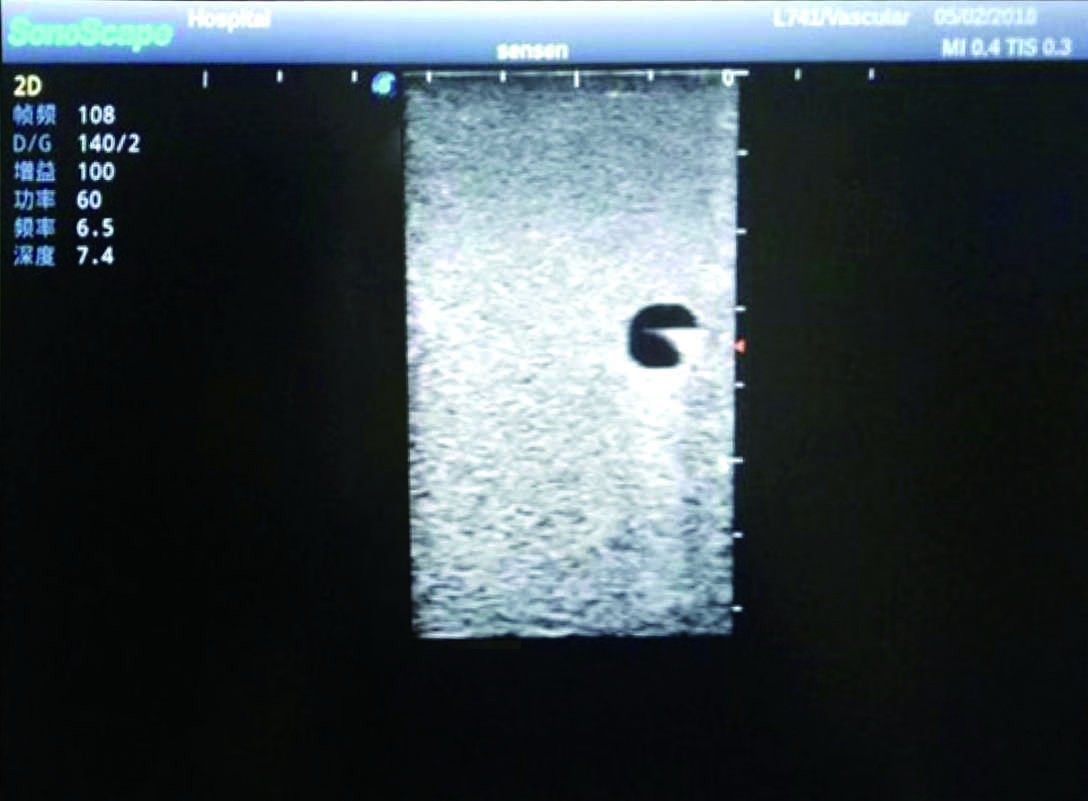

Model TYE1510.1

1)   Made of high molecular polymer ultrasound material, close to the real skin

2)   It can be used by real ultrasound machines

3)   Clear and real images of the tissues and organs (basilic vein and superior vena cava)